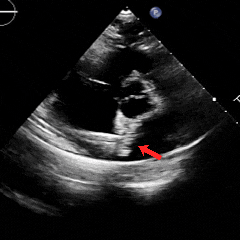

经胸右心声学造影:经左肘静脉注入震荡生理盐水(8mL生理盐水+1mL回抽静脉血+1mL空气经震荡制成),上腔、右房依次显影,造影剂完全充盈右心后,平静呼吸时,左房内即可探及微泡回声,约20-30个/切面/帧;瓦氏呼吸释放即刻,左房内探及微泡回声,不可计数。

术前静息状态经胸右心声学造影(中量)

术前瓦氏动作后经胸右心声学造影(大量)